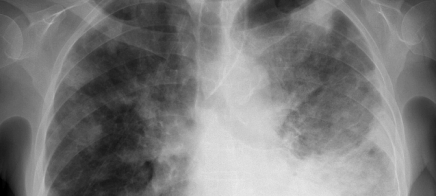

Unklare persistierende disseminierte Infiltrate der Lunge: Anamnese, Diagnostik und Therapie

Unklare persistierende disseminierte Infiltrate der Lunge: Anamnese, Diagnostik und Therapie